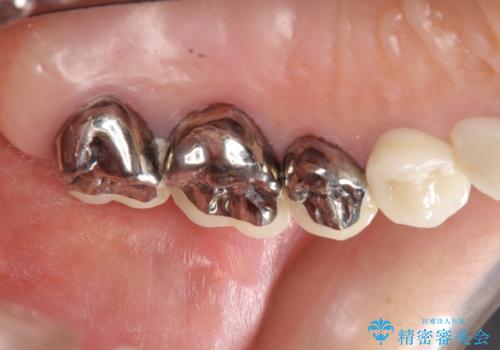

X線写真・視診より歯の破折クラウン下の虫歯再発が認められます。

クラウンの除去・虫歯の除去、根管治療を行ったのち、上顎は強い咬合力に対し破折抵抗性のある咬合面をメタルにしたメタルボンドによる補綴を計画します。